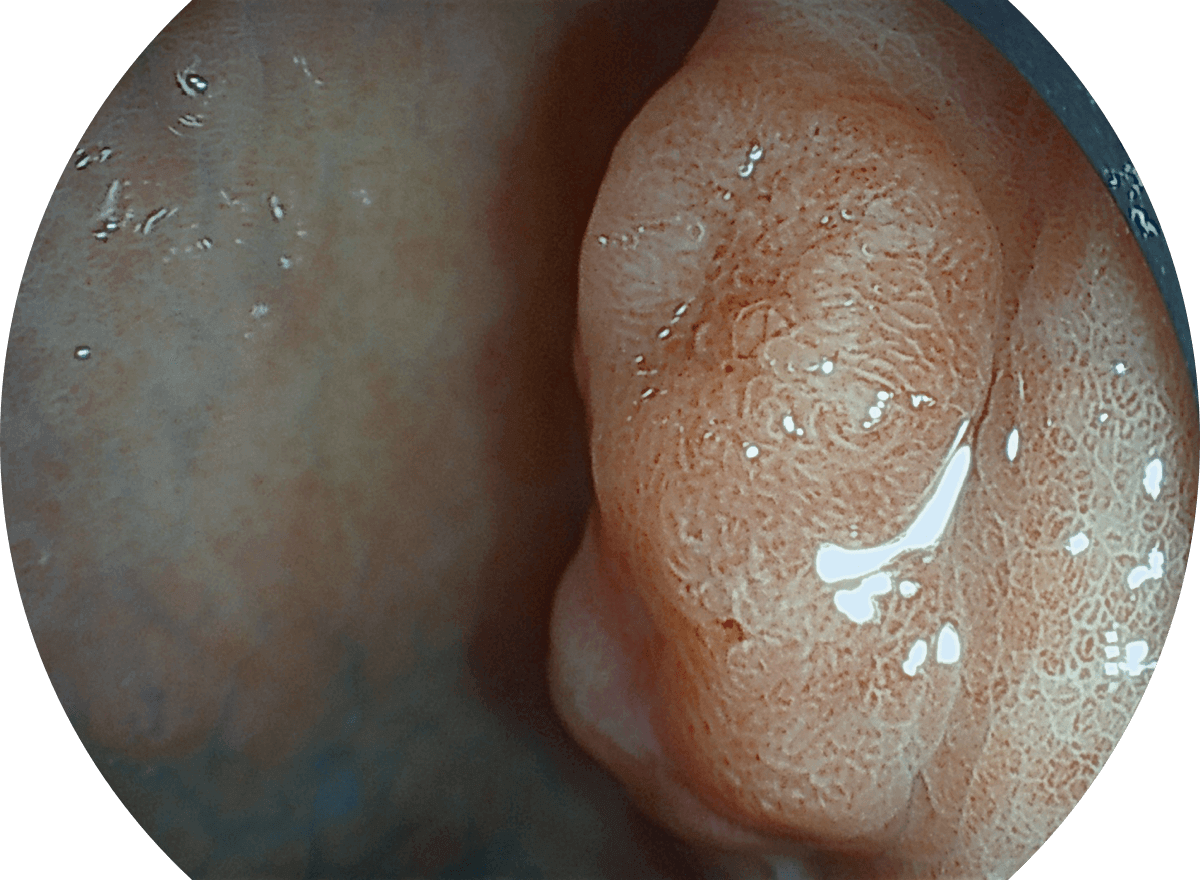

SFI